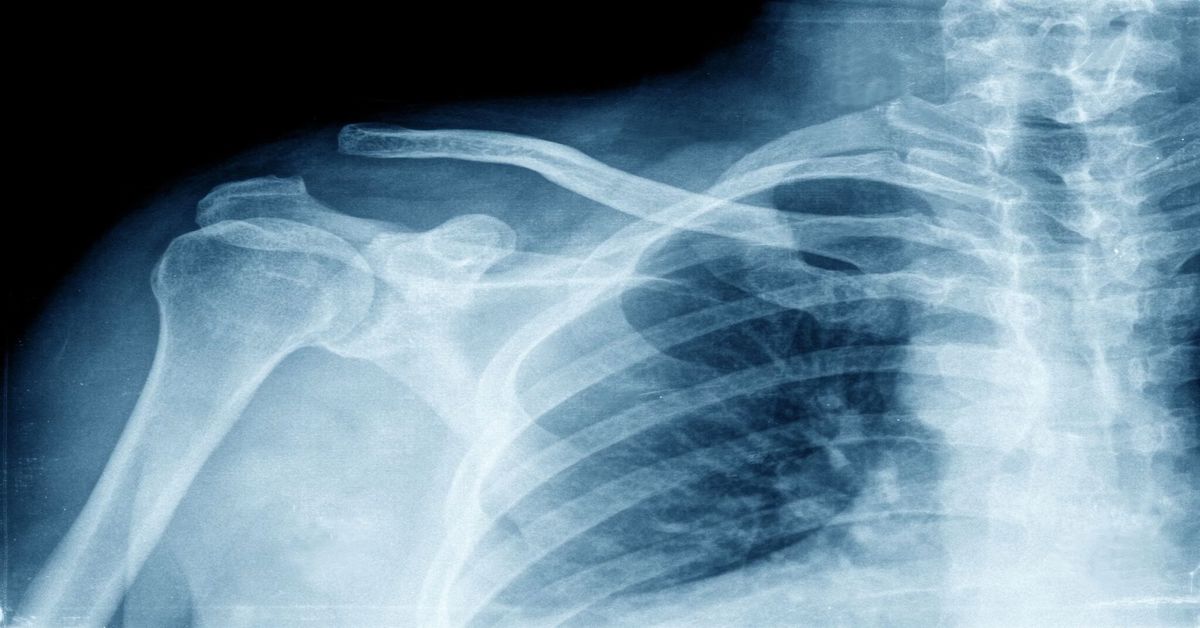

Omuzdaki kemiklerin kırılması, genellikle düşme veya darbeler sonucu meydana gelir. Bu tür bir yaralanma, omuzda şiddetli ağrı, şişlik ve hareket kısıtlılığına yol açar. Omuz bölgesindeki ağrı, hastanın günlük yaşamını olumsuz etkiler ve omuzu hareket ettirmede zorluk yaşanmasına sebep olur.

Omuz kırığı belirtileri arasında en yaygın olanı şiddetli ağrıdır. Bu ağrı, omuz eklemindeki kırıkla doğru orantılı olarak artar. Aynı zamanda, omuz çevresinde şişlik ve morarmalar görülür. Bu durum, kişinin kolunu hareket ettirmesini engelleyebilir. Çoğunlukla ağrılı ve zorlayıcı bir hareketle kendini belli eder.